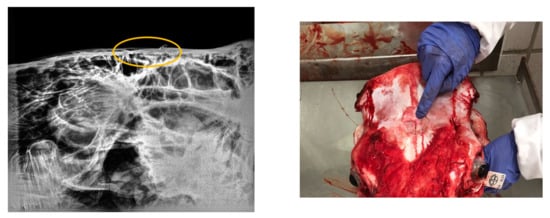

Regarding the radiographical study, it was observed that the skulls presented rating 1 “no visible damage” (70%) or 2 “indentation no cracking” (20%), and rating 3 “indentation with cracking but no displacement” (10%) following the Malaysia Standard (Figure 3, Figure 4, Figure 5). Consequently, 90% of the HSS animals (ratings 1 and 2) would be accepted for halal commercialization. However, no radiographical differences existed between ratings 1 and 2 (Figure 3 and Figure 4); only macroscopic differences in soft tissues were noted.

Figure 5.

Digital radiography rating 3 (following Malaysia Standard 1500:2009). The eclipsed area defines the perimeter of the damaged area. On the right is shown the related photograph.

As Majeed et al. [37] exposed, a beating heart is indispensable for a thorough bleed-out by the animal and attainment of a higher amount of blood at exsanguination is better during halal slaughter according to Shari’ah (halal law). Even if the variation in Islamic jurisprudence is one of the primary determinants of intra-regional trade of halal meat import demand in OIC member countries [38], most certifiers indicate that they accept pre-slaughter stunning if the stunning does not result in the death of animal prior to exsanguination, a Muslim should perform the slaughter and a short prayer must be recited and only manual (by hand) slaughter is acceptable [39]. According to this premise, our findings revealed the halal slaughter with stunning was the best procedure from the microbiological and AW point of view. At present, the Malaysian Protocol for the Halal Meat and Poultry Productions allows the non-penetrative captive bolt stunning for bovine [22] setting a rating scale of 6 grades depending on the skull damage. The radiological study in our research demonstrates the benefits of this stunning method in the tested animals, evidencing the ratings 1 or 2 for 90% of the skulls; this means the halal condition for the carcass.